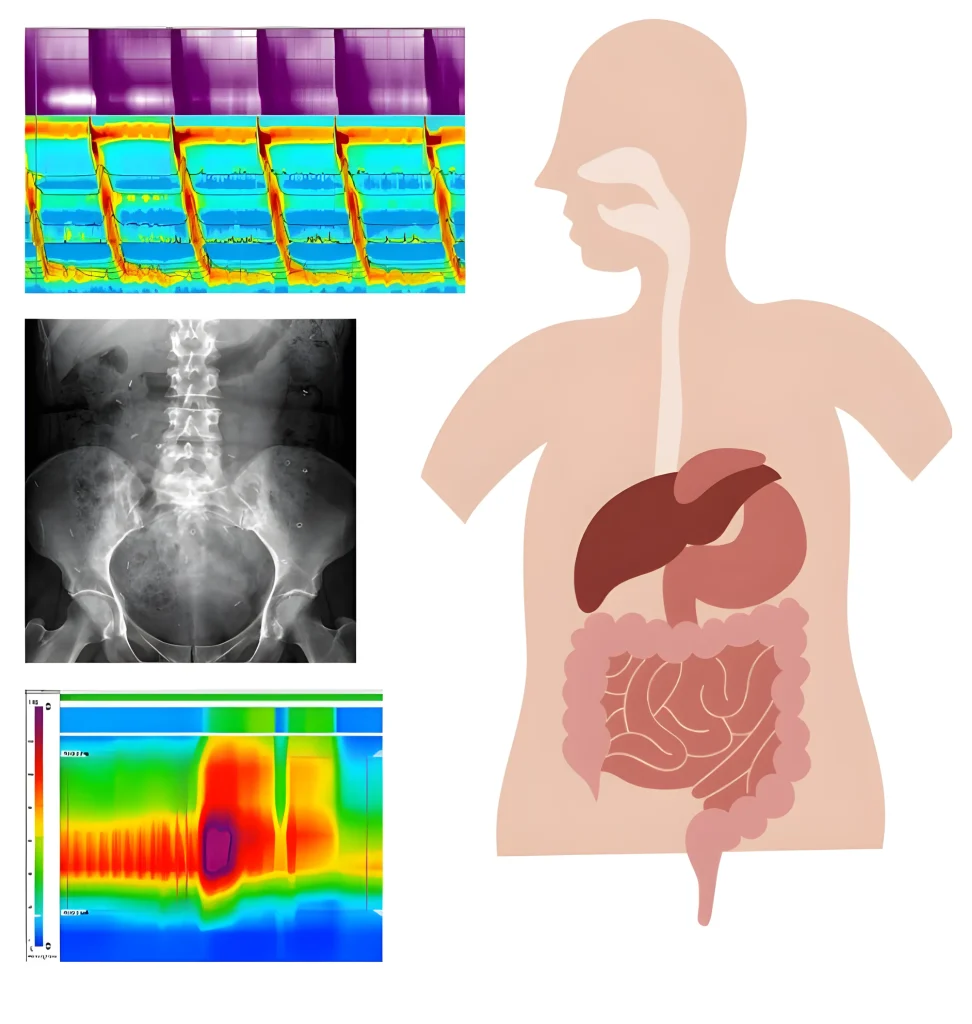

Estudos de Motilidade Digestiva

Nas últimas décadas foi-se dando progressivamente mais importância aos estudos da motilidade como uma tentativa de explicação para os sintomas e doenças do tubo digestivo.

Se bem que muitos dos métodos de estudo da motilidade digestiva sejam ainda de utilização puramente investigacional, existem alguns que, atualmente, jogam um papel fundamental no manuseamento clínico do doente com afecções digestivas.

Estes métodos são frequentemente realizados no nosso laboratório:

• Manometria esofágica convencional

• Manometria esofágica de alta resolução

• Manometria esofágica de alta resolução com Impedância

• pHmetria esofágica ambulatória convencional

• Estudo do refluxo gastro-esofágico ácido e não ácido por impedância esofágica associada a pHmetria esofágica ambulatória

• TelepHmetria

• EndoFLIP – Planimetria com Impedância esofágica

• Manometria Ano-rectal de alta resolução

• Estudo do tempo de transito oro-cecal

• Estudo do tempo de transito do cólon